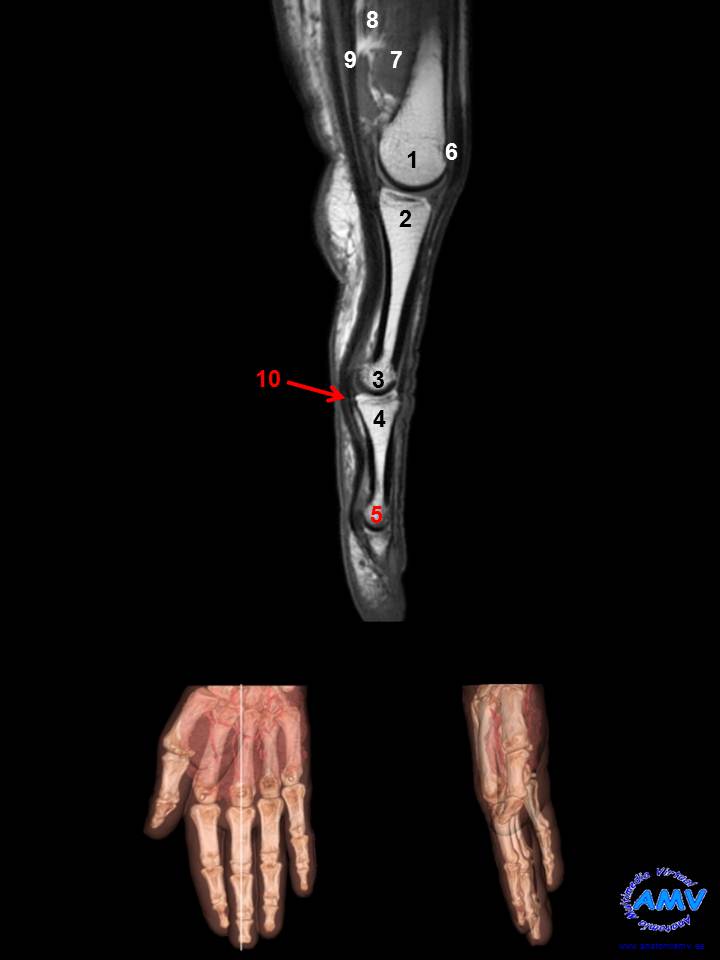

RMN Sagital de Mano

ms_rmn_14.jpgIndique que estructura se señala con el número correspondiente:

El nº 1 señala a la .

El nº 2 señala a la .

El nº 3 señala a la .

El nº 4 señala a la .

El nº 5 señala a la .

El nº 6 señala al tendón del músculo .

El nº 7 señala al músculo .

El nº 8 señala a la cabeza transversa del músculo .

El nº 9 señala al tendón del músculo .

El nº 10 señala al tendón del músculo .